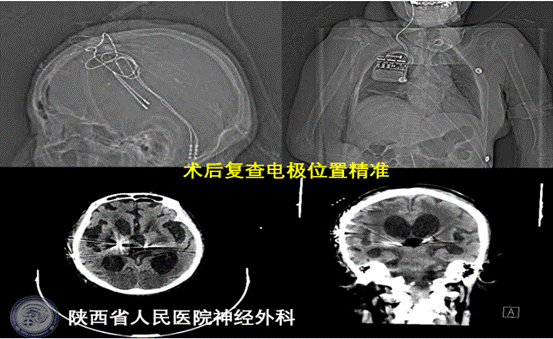

患者车祸外伤后意识不清7月余,大脑缺血缺氧损伤,伤后长期呈昏迷状态,对症康复保守治疗作用不佳,其意识水平长期维持在植物状态,CRS-R评分8分,自发睁眼,存在睡眠-觉醒周期,但无意识内容。患者家属促醒治疗意愿强烈,经过神经外科功能团队系统化的专业评估,完善多次昏迷恢复量表、长时程视频脑电图、多次术前CT及磁共振不同序列等评估,患者接受脑深部电刺激促醒治疗手术指征明确,术前经过严格的手术路径设计,手术靶点标定为丘脑中央中核-束旁核复合体(cm-pf),由于该靶点位置较深,是一个相互传递丘脑皮质信息的丘脑内束,其复合体直径仅约10mm,并且穿刺需避开脑沟脑室,为保证穿刺靶点的精确性,患者于手术当日清晨再次安装Leksell立体定向头架扫描颅脑CT,融合CT与术前磁共振数据并修正靶点坐标,术中精确设计入颅通道后精准定位穿刺靶点,双侧电极及刺激器植入顺利;患者术后再次复查颅脑CT并与术前磁共振影像融合,确认电极精准位置精准;目前患者反应良好,拟于近期开机进行规范化的术后程控促醒治疗。